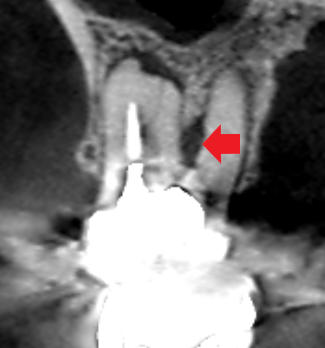

上顎第一大臼歯の頬側2根の矢状断のCT画像です。

上顎第一大臼歯の頬側2根共に根の先に小さい膿の影がみられます。